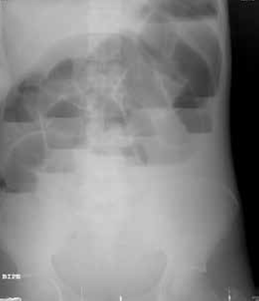

Entre sus exámenes de laboratorio se destacaba una hipopotasemia leve; en el estudio de radiología simple de abdomen, en bipedestación y posición supina, se observó un patrón de ‘pilas de monedas’ (figuras 1, 2, 3).